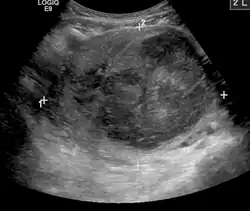

A very large (9 cm or 3.5 in) fibroid of the uterus causing pelvic congestion on US

Chronic pelvic pain

Veins have one-way valves that help blood flow toward the heart. If the valves are weak or damaged, blood can pool in veins, making them swell. When this happens near the pelvis, it is called pelvic congestion syndrome, which can lead to chronic pain beneath the level of the belly button.

Pelvic congestion syndrome usually affects women who have previously been pregnant, because the ovarian veins and pelvic veins had widened to accommodate the increased blood flow from the uterus during pregnancy. After the pregnancy, some of these veins remain enlarged and fail to return to their previous size, causing them to weaken and allowing blood to pool.[42]